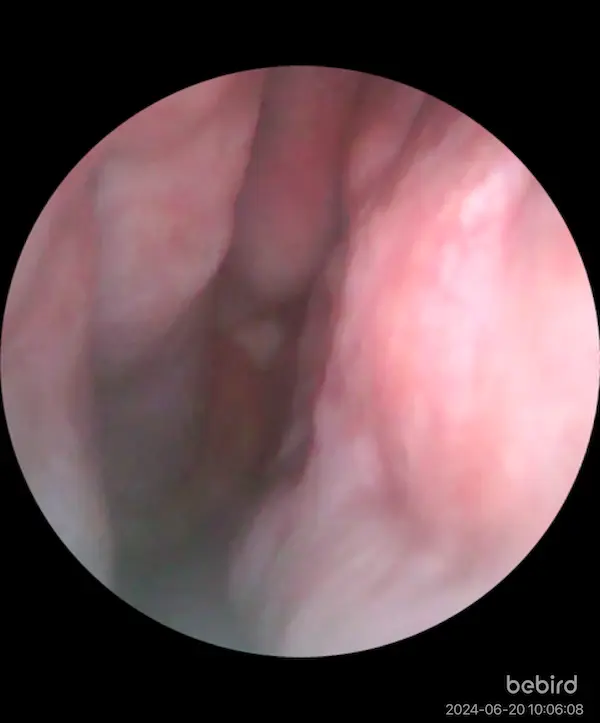

エンプティノーズの手術から8ヶ月経ったが、過去イチで快適だ。 一切のドライ感もないし、1日中完全に通っている。 下鼻甲介自体ないので、アレルギー性の鼻水も出ない。 鼻の学歴はかなり高い。みなさんはどうだろうか。

エンプティノーズ手術前は、もともと夏にあって暑くなってくるとなぜか詰まる という現状があり、最近2度の手術はどちらも、 夏になって鼻詰まりが強くなったことで受診した結果である。 先生に、夏になると詰まるということを言うと不思議がってた。 サウナに入ると鼻が詰まって死ぬほど苦痛だったが、これも消失した。

これはおれの勘だが、 エンプティノーズの場合、鼻腔が広すぎるので 特に夏で外気が暑くなると鼻腔の中のTRPM8が全く活性化されない。 そのため、鼻呼吸の感覚がエンプティになる。 それが手術によって鼻腔を狭めたことによってジェット気流による冷却が発生し、改善したという理屈ではないだろうか。 そして今、鼻腔の冷却具合が夏でも十分になると、 今度は冬に比べて空気が湿っていてドライ感がなくなり、快適になる。 これが、夏になってきて鼻が快適になってきた理由だと思う。 鼻科学は理詰めだ。